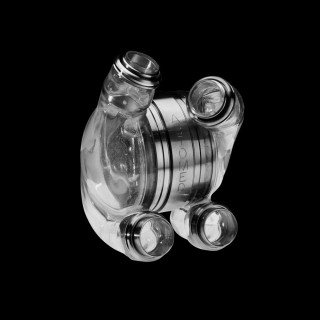

AbioCor Replacement Heart

The AbioCor is the world's first completely self-contained replacement heart. A product of three decades of research, development and testing, the AbioCor is central to ABIOMED's mission to make real the day when heart failure need not mean the end of life or the ability to enjoy life. Designed to fully sustain the body's circulatory system, the AbioCor is intended for end-stage heart failure patients whose other treatment options have been exhausted. A rechargeable internal battery allows the patient to be completely free of the external power transmission unit for some period of time. Normally an external power pack transmits power across the skin.

Patients with an implanted AbioCor heart will still have atria that beat at the same time, but the artificial heart, which replaces both ventricles, can only force blood out one ventricle at a time. So, it will alternately send blood to the lungs and then to the body, instead of both at the same time as a natural heart does. The AbioCor is able to pump more than 10 liters per minute, which is enough for everyday activities.

The AbioCor is primarily made of titanium and Angioflex™, ABIOMED's proprietary polyether-based polyurethane plastic. Angioflex has been developed and tested by ABIOMED to be a dependable substance and safe for contact with blood. The AbioCor is designed to have relatively few moving parts. Moving parts such as the valves and hydraulic membranes are manufactured from Angioflex. Angioflex has proven flexible and durable enough to withstand beating 100,000 times a day (the approximate number of beats per day of the natural heart). The AbioCor's smooth plastic construction and unique design are specifically engineered to reduce the likelihood of damage to blood cells and to prevent clotting.